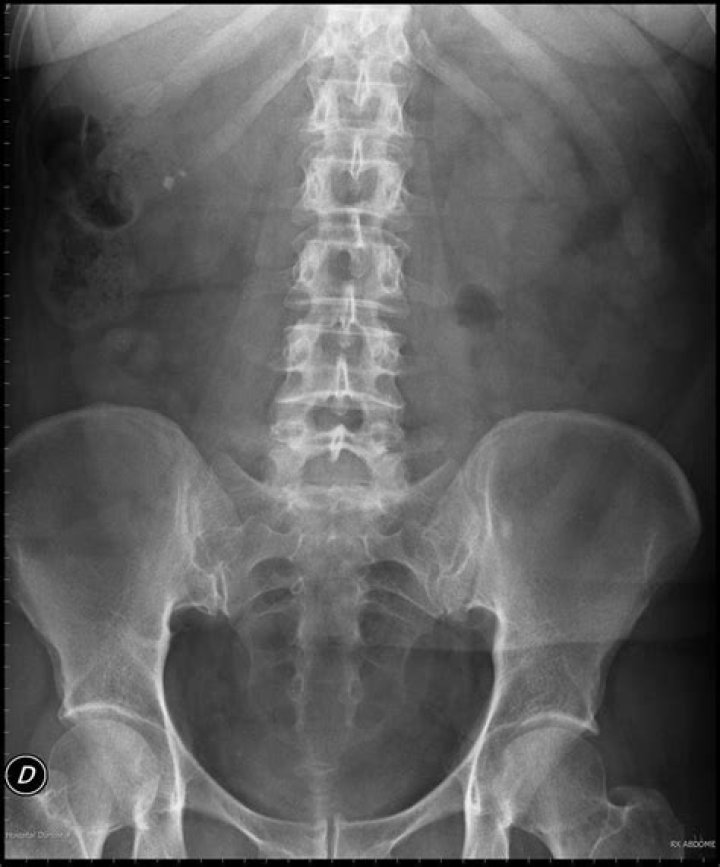

Radiografía abdominal

Es un examen imagenológico para observar órganos y estructuras en el área abdominal, incluyendo el bazo, el estómago y los intestinos.

Cuando este examen se hace para observar las estructuras de la vejiga y el riñón, se denomina radiografía de RUV (riñones, uréteres y vejiga).